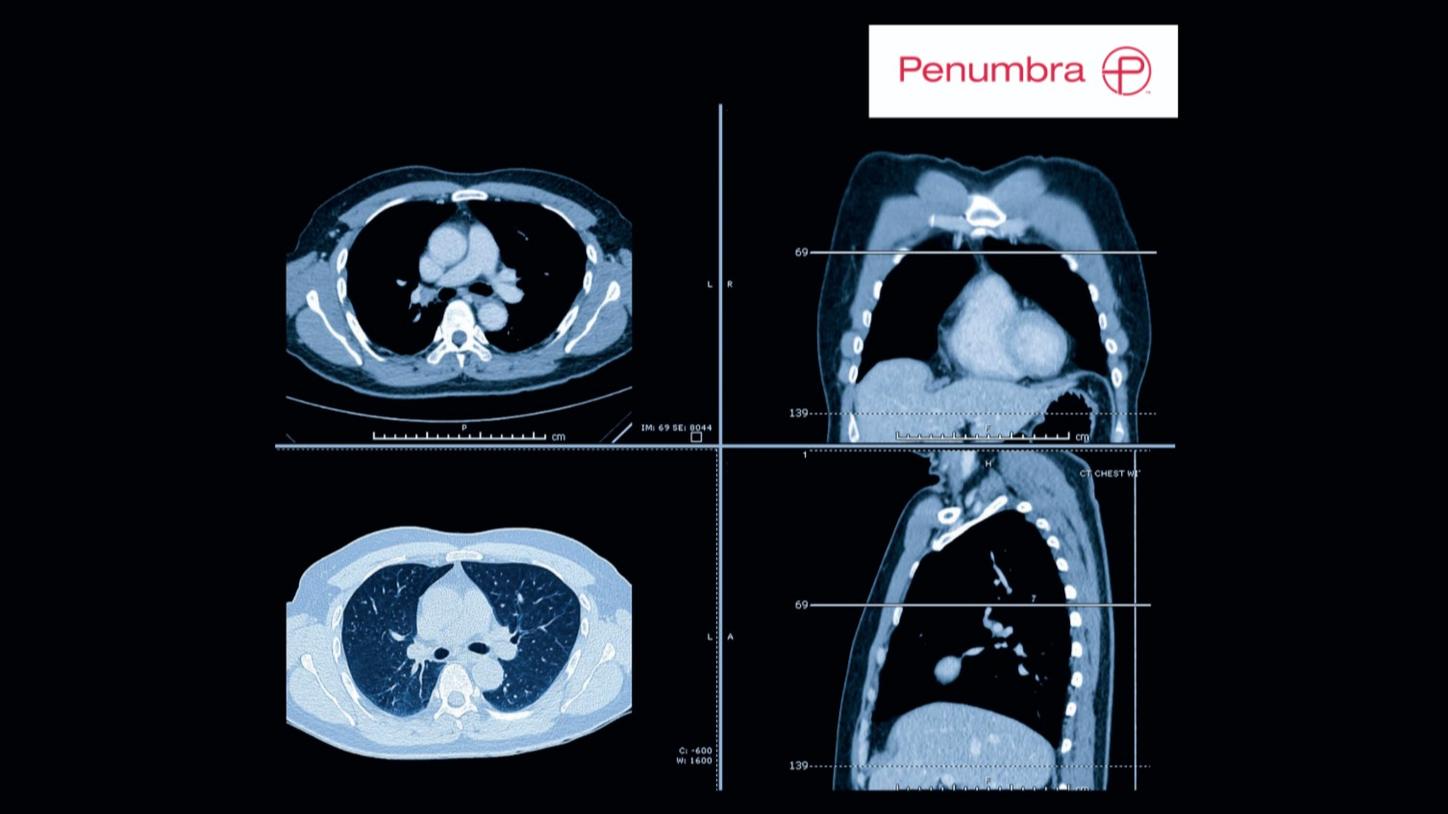

Warsztaty tomografii komputerowej naczyń wieńcowych

Data: 10-11 kwietnia 2026

Kurs poprowadzą:

- prof. Cezary Kępka

- prof. Mariusz Kruk

PROGRAM KURSU

Szczegóły i formularz rejestracyjny podamy wkrótce.

Zaawansowane warsztaty dla elektroradiologów CT: badania kardiologiczne, perfuzja mózgowia oraz badania dwuenergetyczne.

Data: 17-18 kwietnia 2026

- Dominika Borowik – Specjalistka ds. Aplikacji

- Joanna Dobrołęcka-Ciskowska – Specjalistka ds. Aplikacji

- Karolina Kołsut-Rompca – Specjalistka ds. Aplikacji

Formularz rejestracyjny podamy wkrótce.

TK serca w codziennej praktyce

Data: 22-23 maja 2026

- dr n. med. Małgorzata Urbańczyk-Zawadzka

- prof. Ilona Michałowska

- mgr inż. Paweł Banyś